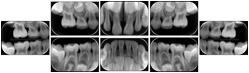

3. A dental provider wishes to capture a series of DICOM IO images for the patient’s dentition. The tooth morphology, teeth are divided into molars, premolars, canines and incisors, and a number of images for each jaw. The anatomic information was captured utilizing the triplet of schema. This standard code sequence is based on ISO 3950-2010, Dentistry - Designation system for teeth and areas of the oral cavity.

Every IO image should have anatomic information either through the primary or modifier sequence.

In most standard cases, images are oriented in structured layouts. These structured displays are useful to be shared between providers for reference purposes.

Table OO.1.1-1 shows structured display standard templates, where Viewset ID is based on the Japanese Society for Oral and Maxillofacial Radiology (JSOMR) classification provided by JIRA (Japan Medical Imaging and Radiological Systems Industries Association, www.jira-net.or.jp). Expected or typical teeth to be imaged location, region and designation codes are based on ISO 3950-2010, Dentistry - Designation system for teeth and areas of the oral cavity. For all the hanging protocols listed in OO.1.1-1, the value to use for Hanging Protocol Creator (0072,0008) is "JSOMR" and the value to use for Hanging Protocol Name (0072,0002) does not include "JSOMR" (e.g., "DL-S001A", not "JSOMR DL-S001A").